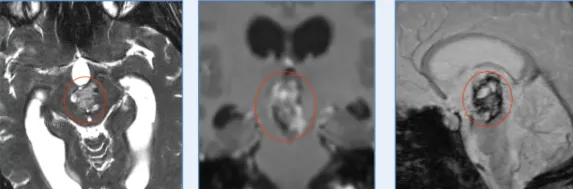

然而,直到医生及家属看清女孩的核磁,冷汗再一次流下:这个巨大的海绵状血管瘤,竟张开血盆大口,“吞下”了整个中脑!

被ICU紧急送往当地医院,发现一个巨大的脑干占位,考虑海绵状血管瘤可能,由于当时已经发生了一次脑干出血,于是L同学被安排在当地医院ICU住院治疗。

中脑位于脑桥之上,恰好是整个脑的中点。中脑是视觉以及听觉的反射中枢。大脑皮层与脊髓间的上行及下行神经通路都经过中脑,同时,中脑通过白质与其他中枢神经系统的分部相联系,正因如此,中脑的病变治疗难度大,难以手术,手术风险极大。而L同学的巨大肿瘤已然将小小的中脑“吞下”,甚至从影像上无法辨认,面对如此困境,L同学该何去何从?